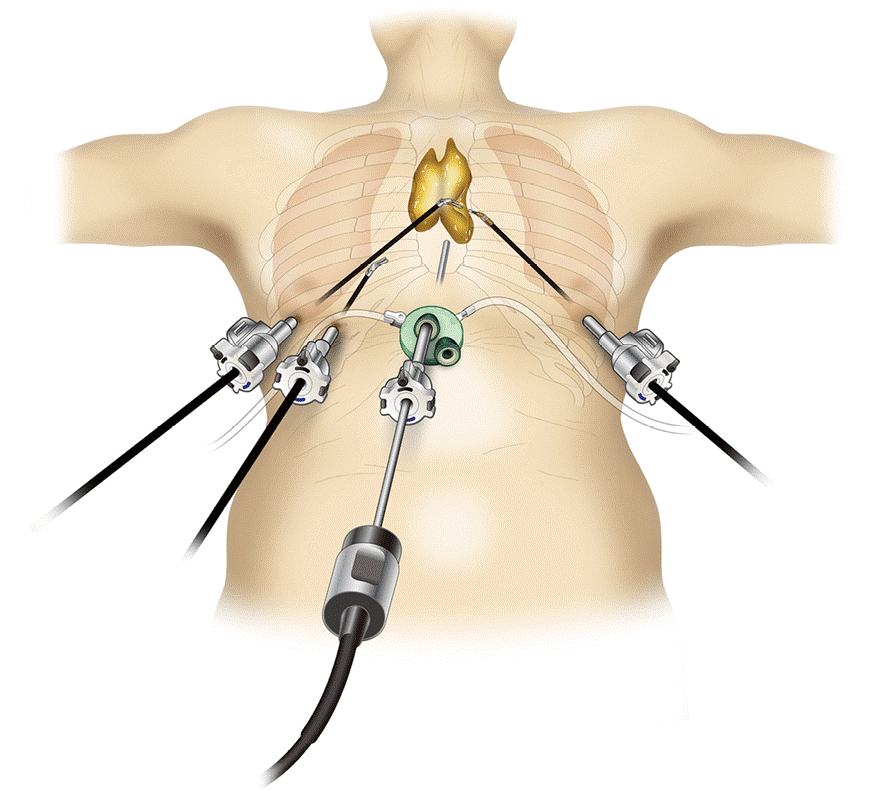

- Тимомы нуждаются в хирургическом лечении. При высокой степени злокачественности за хирургическим вмешательством следует лучевая терапия. Для удаления опухоли используются различные доступы: как минимально инвазивные и роботические операции, так и открытые «большие» операции (торакотомии и стернотомии).